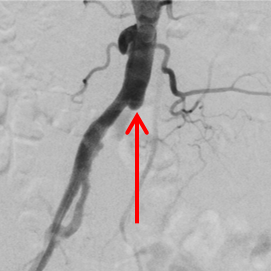

Bild 1a: Verschluss der Beckenschlagader links unmittelbar an der Aufteilung der Körperhauptschlagader (Aorta).